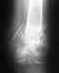

Здравствуйте! можно ли садиться на велосипед послетройного перелома лодыжки со смещением?Прошло три месяца после перелома, по дому хожу без костыля,стоят пластины.